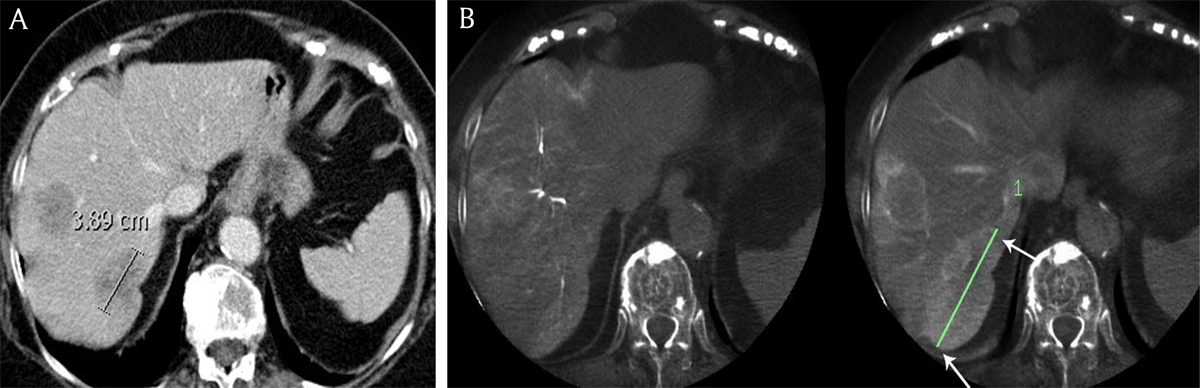

Figure 3

A) Contrast-enhanced computed tomography and B) cone beam computed tomography in an 81-year-old female patient with breast cancer liver metastases demonstrates the longest diameter of the largest metastasis (white arrows), measuring respectively 3.9 cm and 7.9 cm.